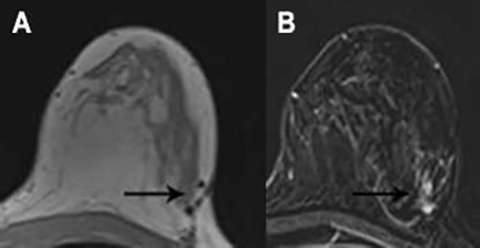

Other than the above, NME within or adjacent to the lumpectomy site is generally suspicious (BI-RADS 4). This includes new or increasing NME, nodular NME measuring greater than 5 mm, mass like enhancement, and NME in suspicious distributions such as segmental, clumped, or regional (Figure 4a and 4b)5. Enhancement kinetics are an important component of the evaluation of NME. Rapid initial enhancement and washout are most concerning for malignancy.